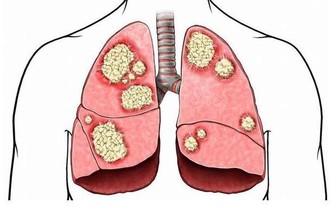

2.預防癌症:青椒含有辣椒素,是一種抗氧化劑,可以阻止細胞組織的癌變,降低癌症細胞的發生率。